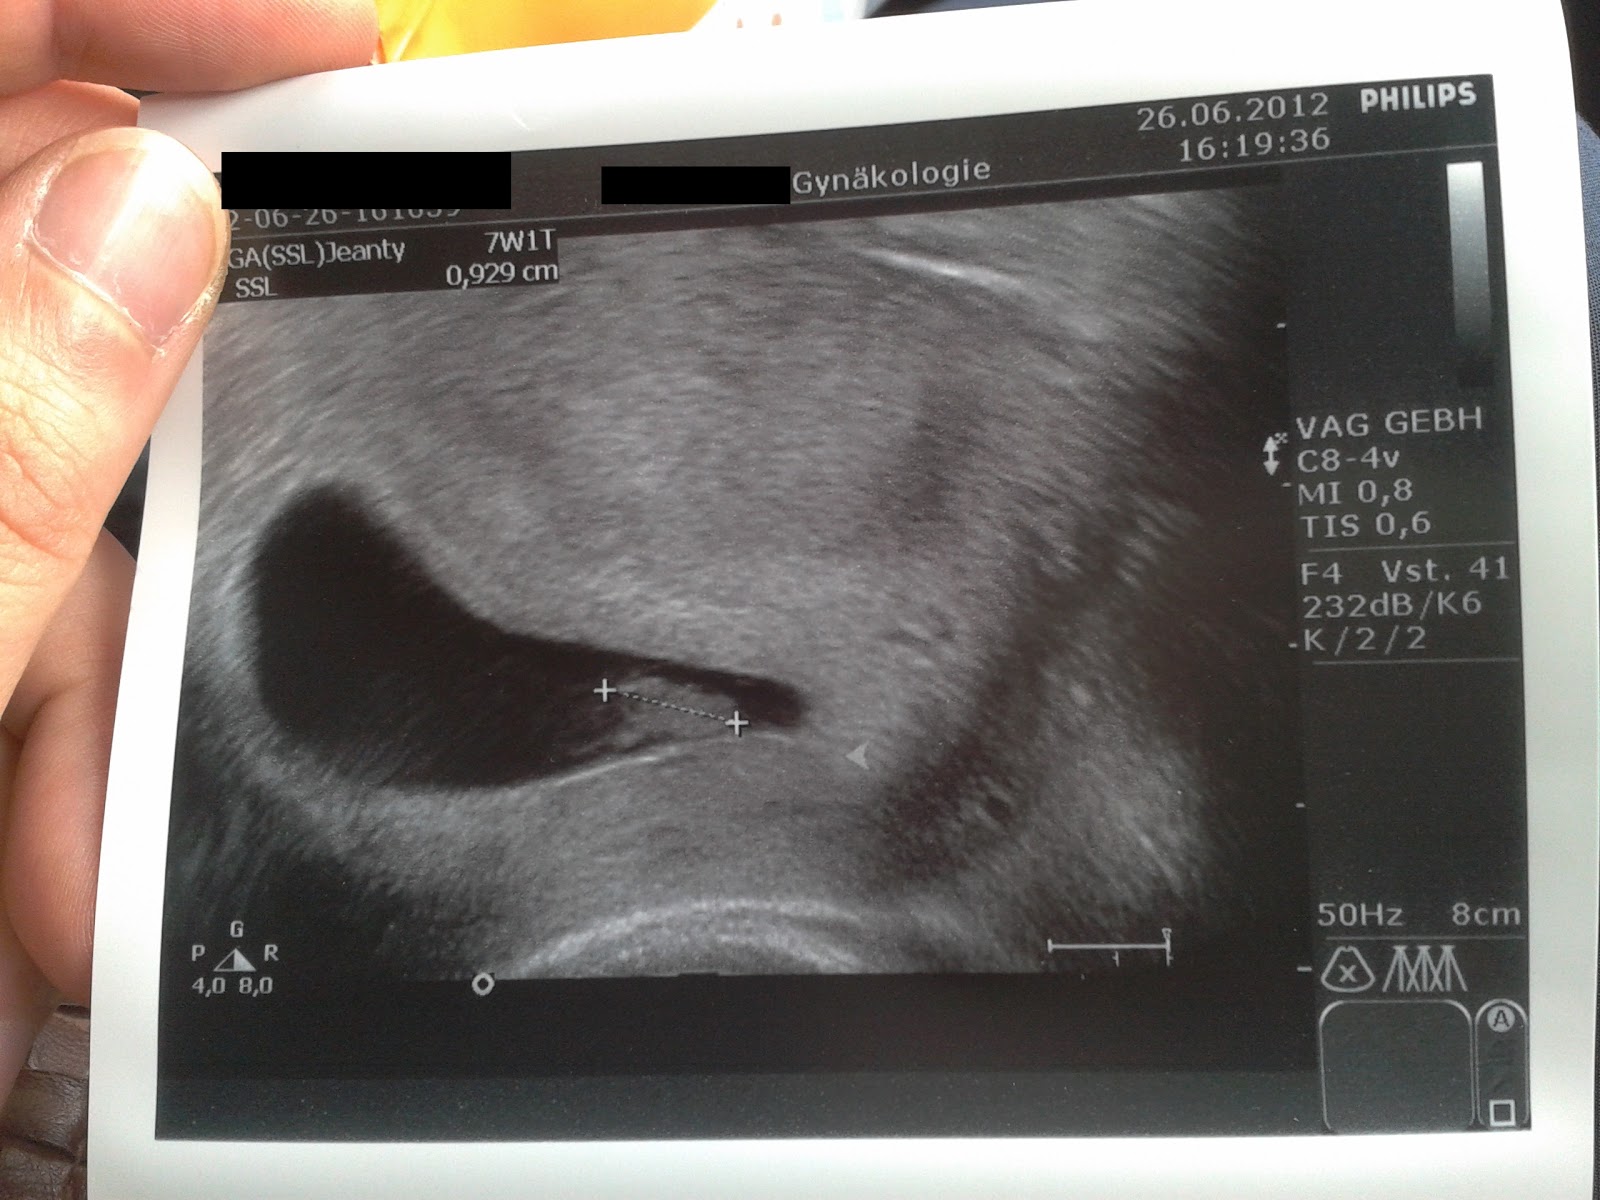

Unseren ersten Frauenartztermin (FA Termin) haben wir am Dienstag hinter uns gebracht und wir durften ein kleines, weißes und pulsierendes Herzchen bewundern. Ein Tränchen lief über meine Wange und wenn der werdende Papa es nicht zugeben will, auch er war sichtlich ergriffen und musste heftig schlucken.

Und zum Schluß noch ein Bildchen des kleinen Bauchbewohners: